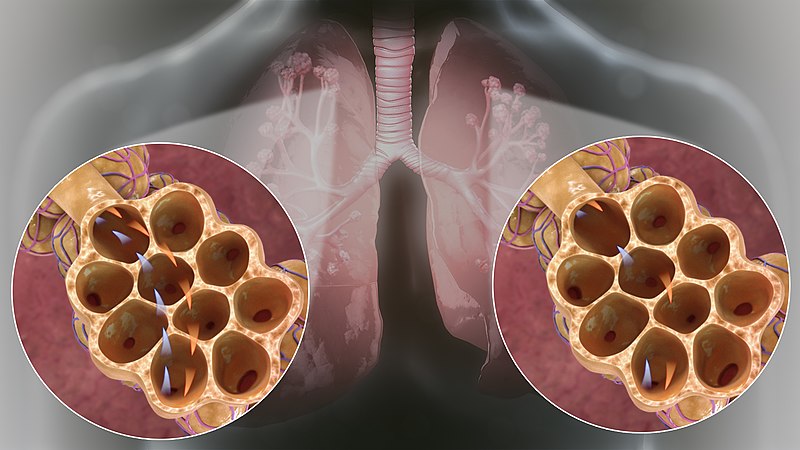

For distinction from neonatal respiratory distress syndrome, acute respiratory distress syndrome was also labelled as adult respiratory distress syndrome (ARDS). It involves inflammation in the lung parenchyma, increased alveolar permeability, reduced lung compliance and non-functional gas exchange. The increased alveolar permeability allows fluid to build up which in-turn prevents the lungs from filling up air, causing less oxygen in the bloodstream. The oxygen deprivation sequentially leads to organ failure. Low blood-oxygen levels in the bloodstream not only affects the lungs but, also harms other organs in the body and prevents oxygen from reaching them for normal functioning. The intensity of the disease can be determined by measuring and comparing blood-oxygen levels. ARDS is a rapidly developing and potentially fatal lung disease, most people don’t survive ARDS. ARDS survivors mostly have lasting damage to their lungs. The risk of death and the severity of the disease increases with age. The main symptom of ARDS is distressing shortness of breath, which develops within the first couple hours and lasts longer than the illness and the duration of recovery.

Type I: – involves a ventilation/perfusion mismatch that causes untreatable hypoxemia (PaO2). Another characteristic of type I respiratory failure is alveolar flooding.